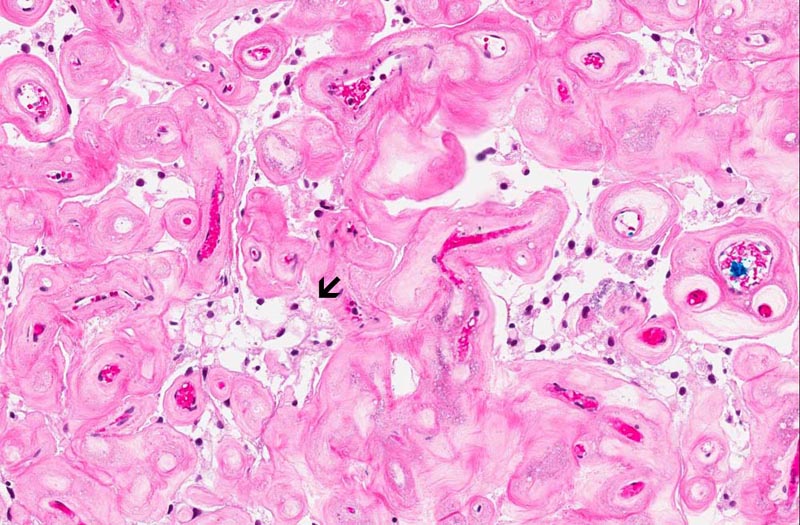

Slide #2 represent the tissue that are

submitted subsequently. The histopathology between this sample and

slide #1 is essentially similar but the there are a lot more highly

sclerotic blood vessels. Some calcifications consistent with

psammoma bodies are present (area 3). The sclerotic blood vessels

dominated the picture. In between the sclerotic vessels are

triangular to irregular nest of stromal cells (area 3). Microcyst

formation is rather common (area 4 and 5).

The overall histopathologic picture is

that of an angiomatous meningioma. These tumor are featured by

hypervascularity and often with degenerative changes of the vessels

including vascular hyalinization as illustrated in this case. The

nuclei tends to undergo degenerative atypia (ancient changes)

featured by slightly enlarged, homogeneously hyperchormatic nuclei

without prominent nucleoli and not associated with increased

mitosis. The neoplastic meningothelial proliferation often has microcystic

pattern as illustrated here.